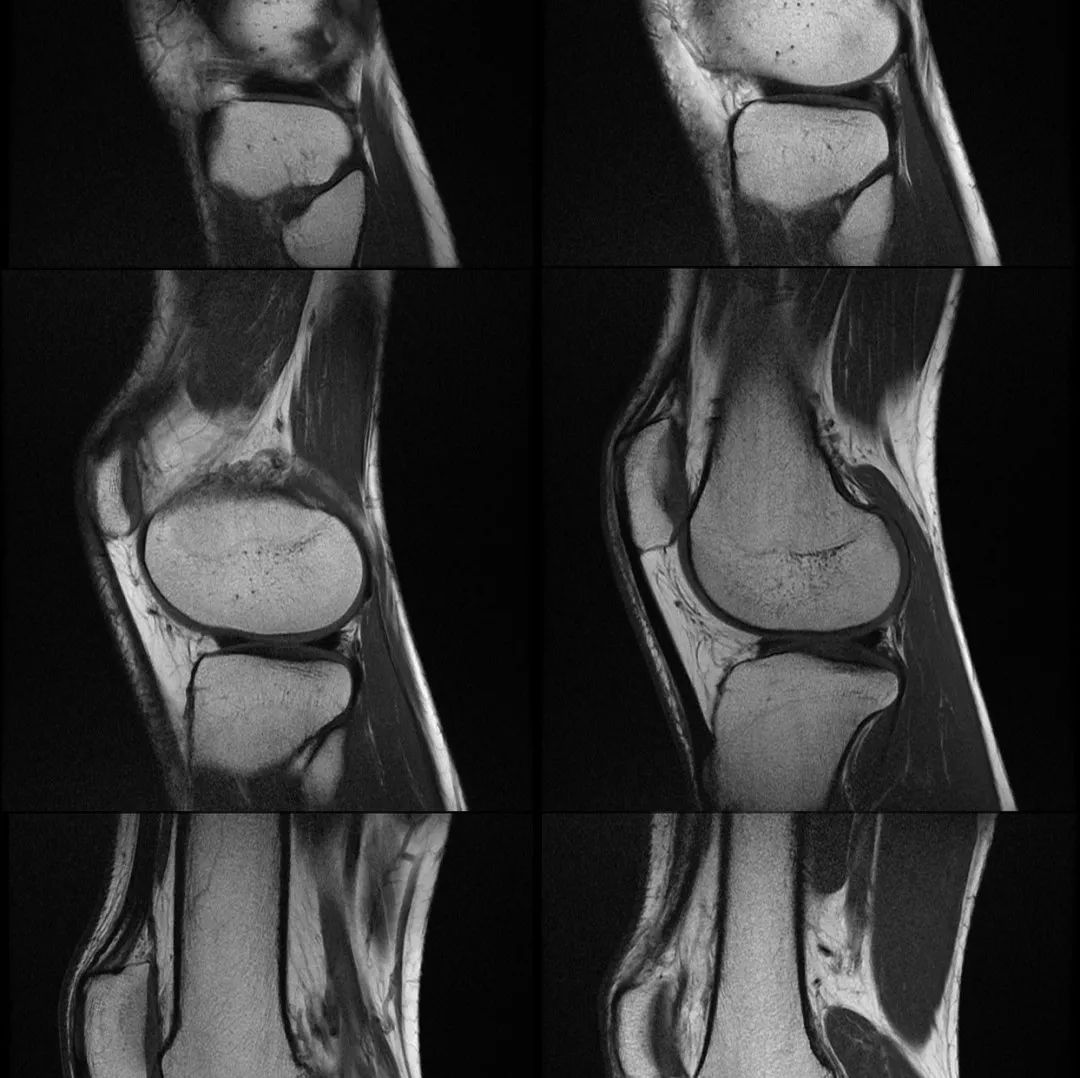

影像时间病例展示患者,女性 ,24 岁主诉:右膝关节外侧反复疼痛不适半年余,近一个星期疼痛加重。现病史:患者右膝关节外侧间歇性疼痛不适半年余,近一个星期疼痛加重,屈膝时明显,门诊行膝关节 X 线片检查,未见明显异常。患者否认手术史/外伤史。为进一步明确情况,我们建议患者行膝关节磁共振检查;图像如下:T1T2 压脂冠状位轴位大家是否发现什么异常?该患者是膝外侧疼痛不适的症状,我们重点观察了外侧半月板及外侧副韧带,但是我们发现是正常的;...